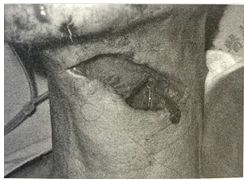

99.如下圖的傷口,應該被描述成? (A)挫傷 (B)穿剌傷 (C)剝離傷 (D)撕裂傷

101.如下圖的傷囗,應該被描述成? (A)挫傷 (B)撕裂傷 (C)剝離傷 (D)穿剌傷